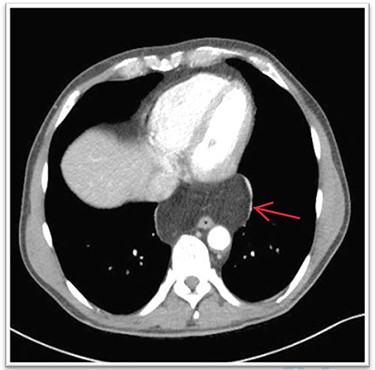

A 63-year-old male patient underwent a medical check-up due to acute bronchitis. The patient’s body mass index was 24.7 kg/m2, he was in good physical condition and no further pathological findings were revealed during clinical examination. Chest X-ray showed a retrocardiac mass (Fig. 1) and a subsequent CT scan indicated a lipomatous mass in the lower posterior mediastinum measuring 10 × 4.4 × 10.6 cm. A vascular pedicle reaching into the abdominal cavity suggested paraesophageal herniation of a large portion of the greater omentum (Fig. 2). The patient was referred to the surgical department suffering from a retrosternal feeling of pressure aggravated in supine position, with a differential diagnosis of lipomatous tumour. No symptoms of gastroesophageal reflux disease were reported, and the clinical examination showed no abnormalities. Preoperative work-up included a gastroscopy and contrast medium swallow. Endoscopy showed an axial hernia of 4 cm without further irregularities or signs of a reflux disease. Passage appeared physiological with no signs of gastroesophageal reflux and orthotopic positioning of the oesophagogastric junction.